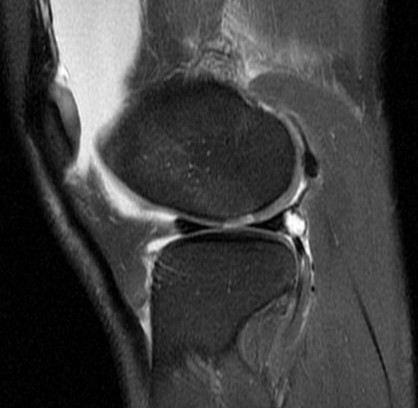

25 y/o twisting injury

Torn mid medial patellofemoral ligemnt, chondral defect of the lateral femoral condyle and medial patella. Displaced chondral fragment adjacent to the lateral femur within the lateral joint space. Also has trochlear dysplasia type B with a subtle supratrochlear spur and an increased tibial tubercle central trochlear distance.

Patellar dislocation